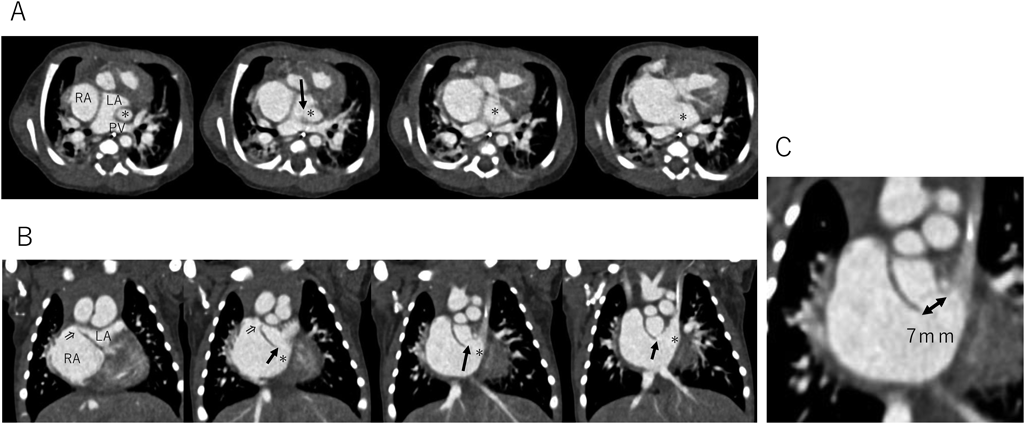

致命的となりうるunroofed coronary sinusの自然閉鎖を認めた僧帽弁閉鎖合併単心室例Spontaneous Closure of a Potentially Fatal Unroofed Coronary Sinus in a Case of Mitral Valve Atresia with a Single Ventricle